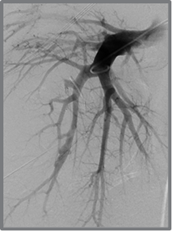

Cas 2 : Pseudo-anévrysme sur branche sous-segmentaire de l’artère pulmonaire droite

après multiples drainages pour infection pleuro-pulmonaire sévère. Contrôle avant et après

embolisation par coil.